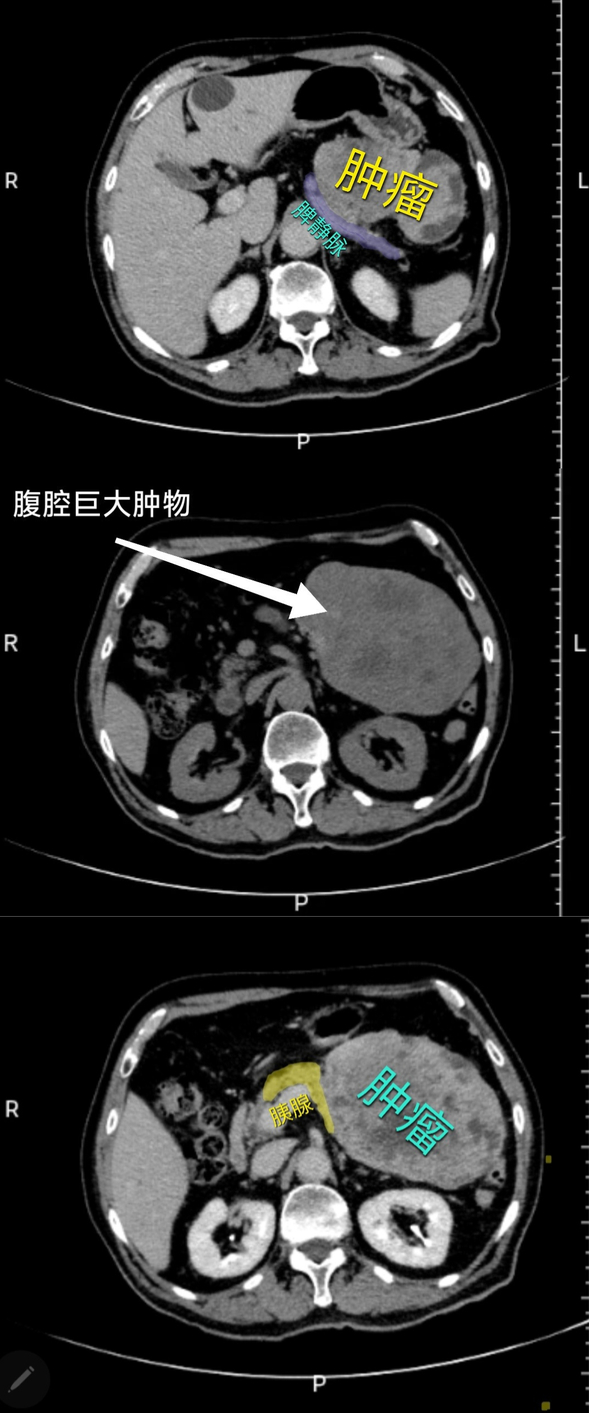

患者因体检发现腹部巨大肿物(约15×12cm)入院。影像学检查一度提示肿瘤来源存疑(倾向胰腺体尾部或肠系膜)。我院普外三科主任邵学谦凭借丰富经验与细致分析,在术前讨论中做出关键判断:该肿瘤极可能来源于胃部。这一基于肿瘤位置、活动度及毗邻关系的深度分析,为后续高风险手术精准导航。

术前腹部CT

据了解,肿瘤直径远超10厘米,血供丰富,剥离中大出血风险极高;其深藏左上腹,紧邻胃、胰腺、脾脏及横结肠系膜等要害器官与血管;术前影像与术中探查均证实肿瘤与胃底、胰腺、横结肠系膜形成广泛致密粘连,分离如履薄冰。加之患者74岁高龄,器官功能储备下降,对手术创伤、麻醉及失血的耐受能力显著降低,围手术期并发症风险剧增。

术后病理诊断为(胃底巨大肿瘤)胃肠间质瘤(GIST),体积达15.3×12×6cm。这一“金标准”完美验证了邵学谦主任术前“胃源性”的精准判断。明确的高危分级也凸显了手术的及时与关键——R0(完全)切除是此类高危GIST患者获得治愈可能的核心一步。